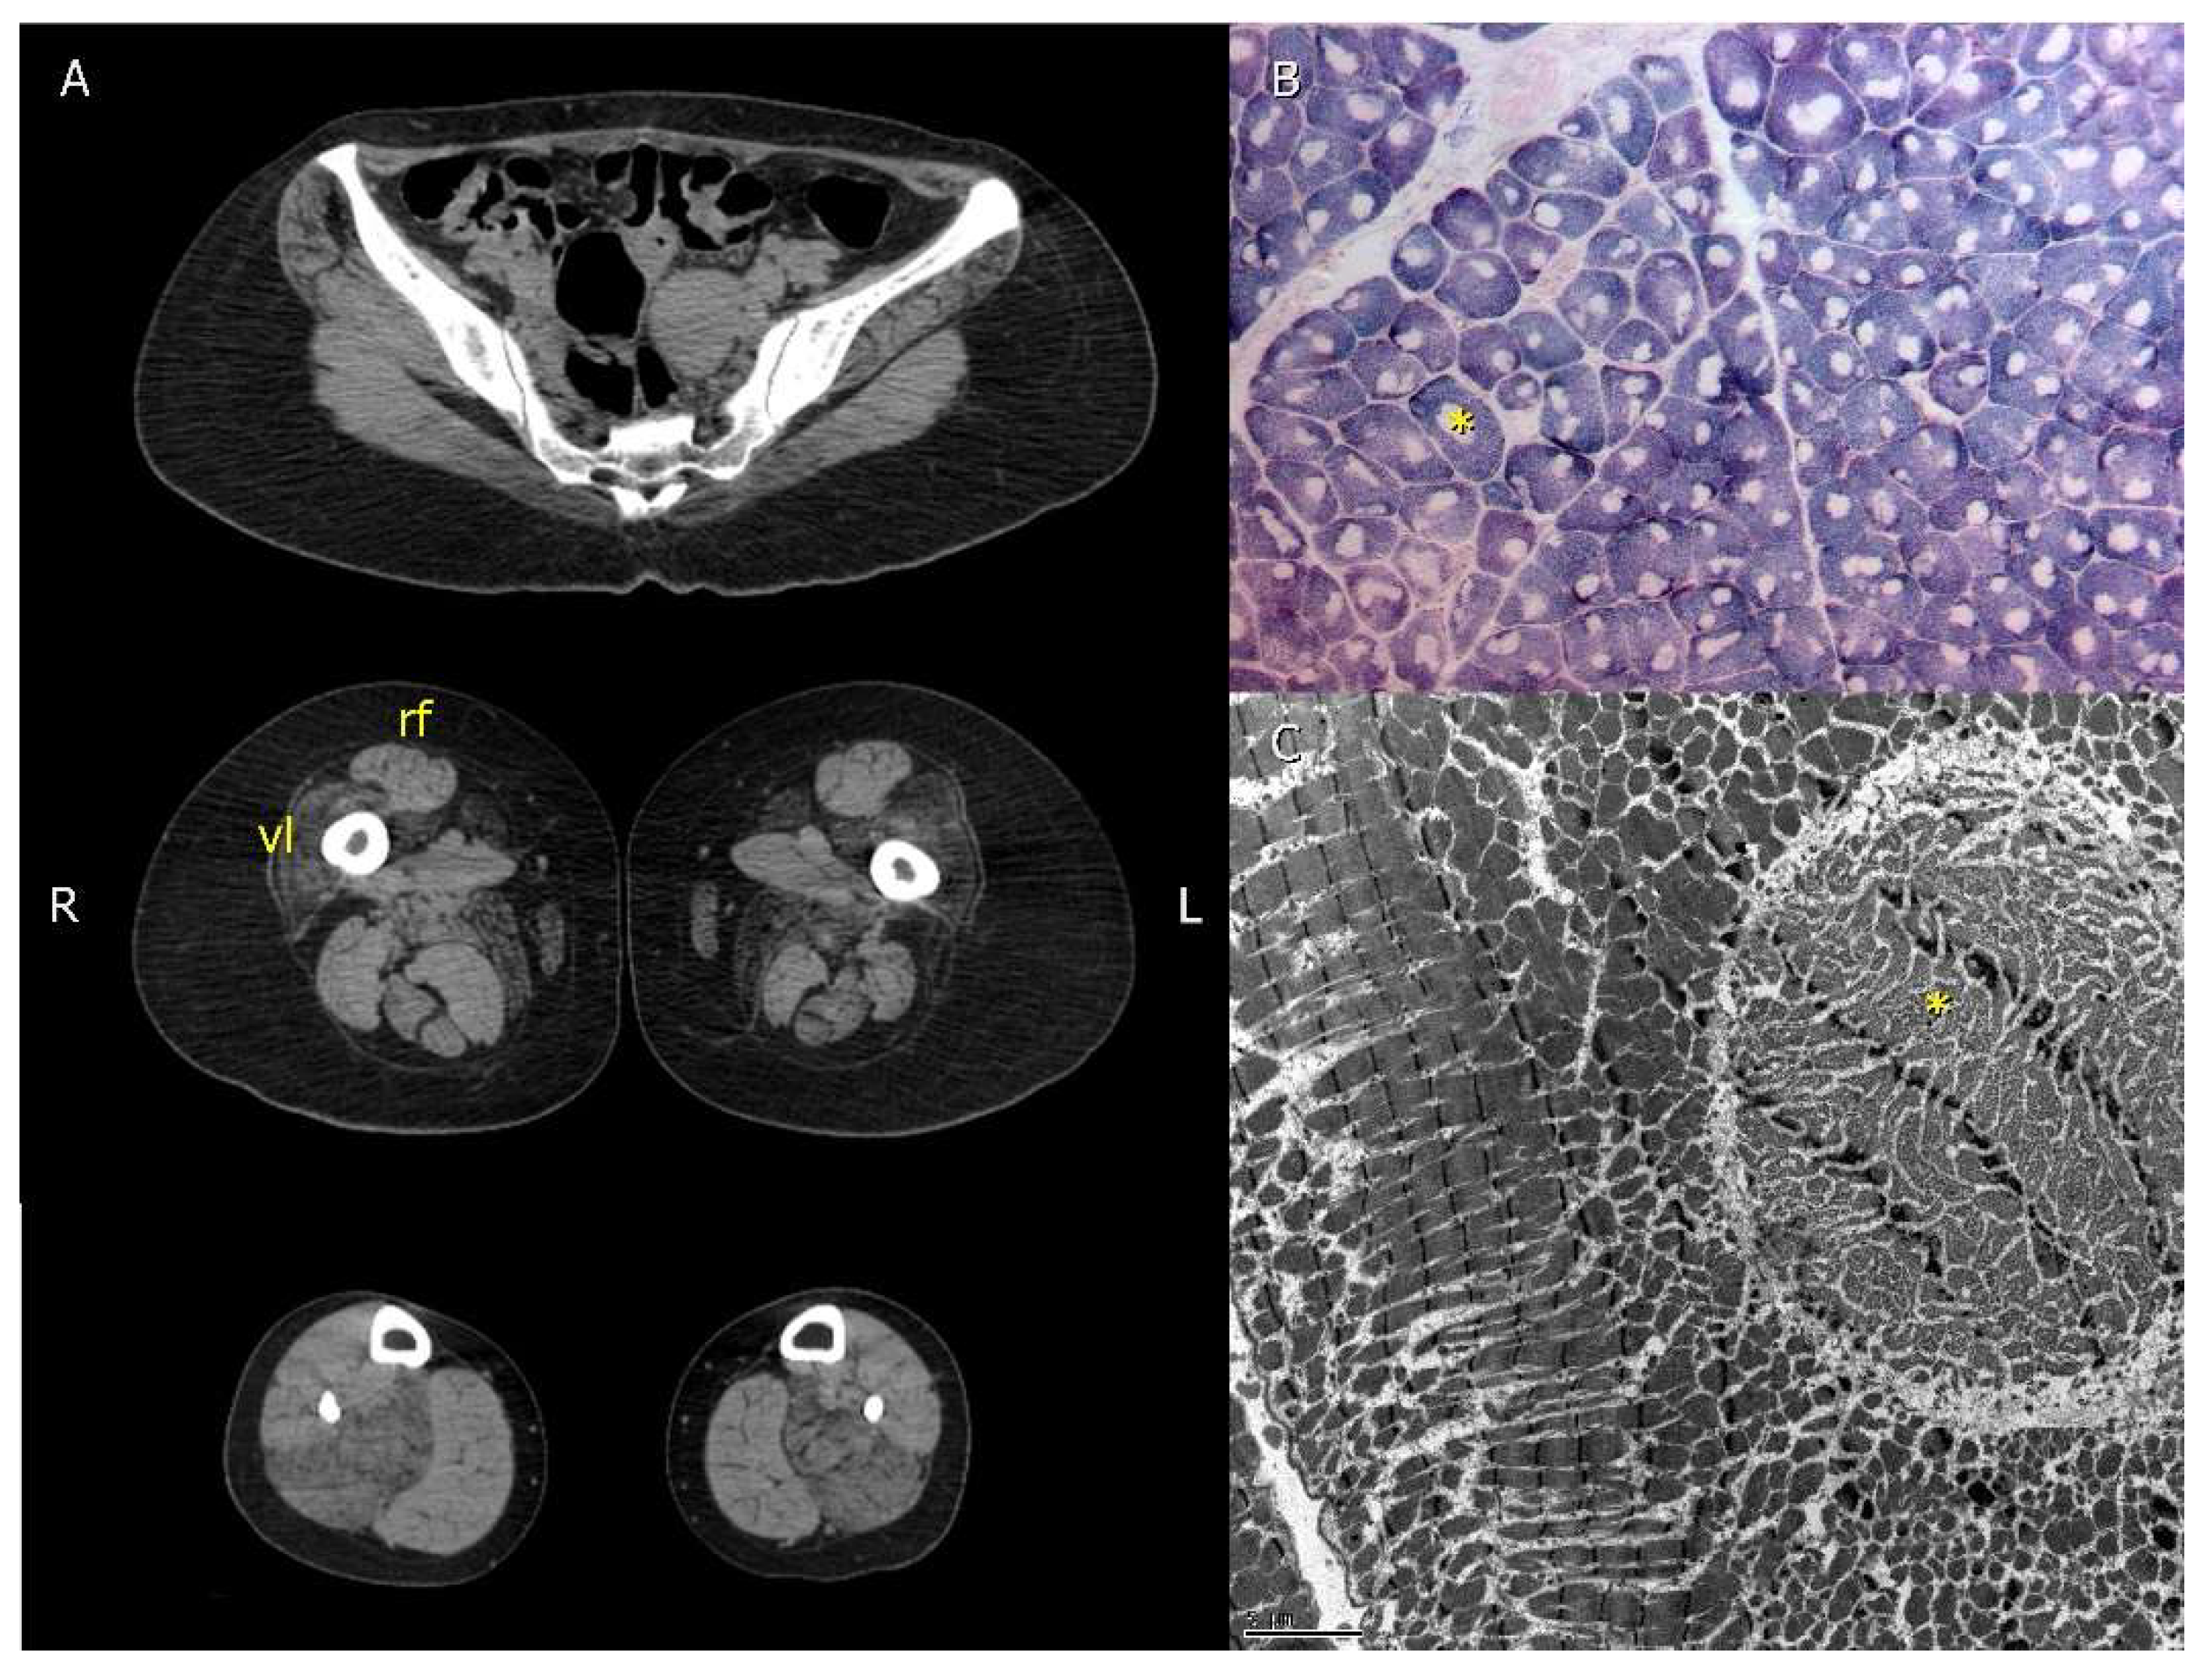

Imaging studies were used to guide the choice for the best site for muscle biopsy. Due to the frequent muscle fat replacement of the vastus lateralis, the rectus femoris was the muscle of choice whenever the former was involved (Figure 2A).

Figure 2.

Imaging and muscle biopsy findings of patient 2.1 with the p.Gly4897Asp pathogenic variant in the RYR1 gene. (A)—Computed tomography demonstrated severe right vastus lateralis (vl) muscle fat replacement with relative rectus femoris (rf) preservation. Computed tomography of the pelvis, thighs, and legs. (B)—Muscle biopsy was performed in the rectus femoris demonstrating round core structures (*). SDH 100x. (C)—Core areas (*) were ultrastructurally characterized by myofibrillar disorganization with scarce mitochondria. Transmission electron microscopy 2500×. This figure was modified from Cotta et al., 2021 [].

All patients submitted to muscle biopsy presented areas devoid of oxidative reaction correspondent to myofibrillar disorganization with scarce mitochondria (Figure 2B,C).